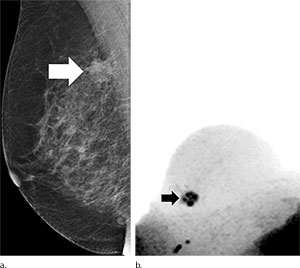

For the new study, researchers in Germany evaluated an abbreviated MR breast imaging protocol that requires no contrast agent. The protocol uses only two short sequences: the first to show the shape and appearance of the lesion and the second to display its biophysiological properties with diffusion-weighted imaging with background suppression magnetic resonance mammography (DWIBS-MRM), a technique that works by assessing the diffusion, or movement, of water molecules through tissue. Areas of restricted diffusion may indicate malignancy.

The researchers compared DWIBS-MRM to an abbreviated contrast-enhanced MRI and full diagnostic breast MR protocol in 50 women with suspicious screening mammograms and indication for biopsy.

Twenty-four of the 50 participants had a breast carcinoma. DWIBS-MRM achieved a comparable accuracy to that of the full diagnostic and the abbreviated contrast-enhanced MRI protocols. The technique yielded an excellent negative predictive value of 92 percent. Negative predictive value represents the probability that a person with a negative test does not have the disease.

DWIBS-MRM has advantages over other MR approaches, Dr. Bickelhaupt said. The MR images can be obtained in less than seven minutes, compared with more than 30 minutes for a full breast MR protocol. The mean reading time using the unenhanced DWIBS-MRM method is less than 30 seconds thanks to an innovative summation technique called maximum intensity projection, or MIP, that allows lesion assessment by reading one summation image instead of multiple single-slice images.